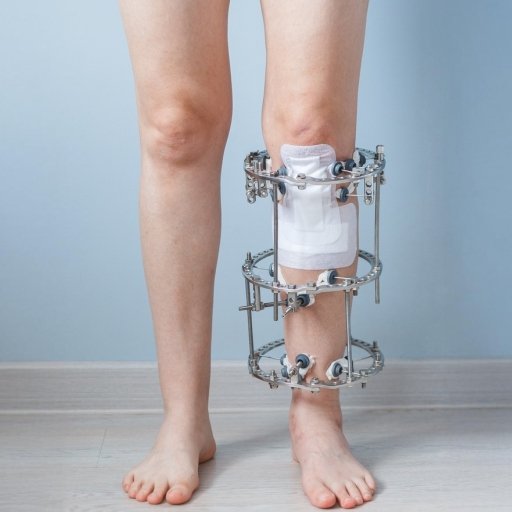

Real Surgical Applications

Our orthopedic implants and surgical instruments are trusted by surgeons in real operating room environments. Designed for precision and reliability, our products support accurate implant placement and improved patient outcomes.